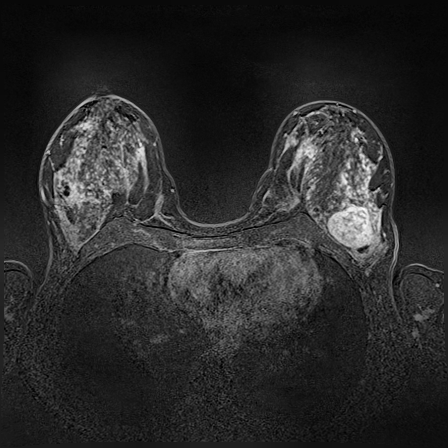

Magnetic resonance imaging (MRI) is an effective imaging modality for identifying and localizing breast lesions in women. Accurate and precise lesion segmentation using a computer-aided-diagnosis (CAD) system, is a crucial step in evaluating tumor volume and in the quantification of tumor characteristics. However, this is a challenging task, since breast lesions have sophisticated shape, topological structure, and high variance in their intensity distribution across patients. In this paper, we propose a novel marker-controlled watershed transformation-based approach, which uses the brightest pixels in a region of interest (determined by experts) as markers to overcome this challenge, and accurately segment lesions in breast MRI. The proposed approach was evaluated on 106 lesions, which includes 64 malignant and 42 benign cases. Segmentation results were quantified by comparison with ground truth labels, using the Dice similarity coefficient (DSC) and Jaccard index (JI) metrics. The proposed method achieved an average dice coefficient of 0.7808 0.1729 and Jaccard index of 0.6704 0.2167. These results illustrate that the proposed method shows promise for future work related to the segmentation and classification of benign and malignant breast lesions.

MR images for this study were acquired on 1.5 T scanners Magnetom Avanto and 3.0 T Magnetom Verio, Siemens Healthineers, Erlangen, Germany, with dedicated breast array coils and the patient in a prone position. The contrast media was applied into the cubital vein after the first of six dynamic acquisitions with a flow of 1.0 mL/sec chased by a 20 mL saline flush. One hundred and six lesions were identified from a representative set of DCE-MRI exams from 80 female patients by two expert radiologists who have 7 years of experience in evaluation of clinical findings. The mean patient age was 50 13 and based on histopathologically 42 of the lesions were diagnosed as benign and the remaining 64 as malignant.

The proposed method starts with selecting a particular slice of breast MRI volume, performed by an expert radiologist, such that it contains at least one lesion. The slice image is normally the subtraction of pre-contrast and post-contrast images. The ground truth segmentation provided by expert radiologists and ROI is drawn around the lesion manually. As a pre-processing step, We applied contrast limited adaptive histogram equalization (CLAHE) [12] on that particular slice globally to improve lesion contrast. Then we computed the morphological gradient of the image, which is the point-wise difference between a unitary dilation and erosion.

In MR images, tumor regions are normally brighter and have more uniform intensity than the neighbouring healthy tissue. Based on this fact, we determined the internal and external markers by sorting out the pixel values in ROIs in descending order and chose pixels with maximum intensity values as markers. After selecting the markers the normal watershed transformation is applied on the ROIs image which is shown in Fig 1 Finally, a binary mask is generated based on watershed output regions. However, we identified the optimal number of markers based on segmentation accuracy evaluated using Dice and Jaccard.

where refers to the ROIs segmented by our algorithm and is tumor area as determined by manual segmentation. Table 1 summarizes the segmentation accuracy achieved using the proposed method for all 106 cases. The average dice coefficient was found to be 0.780.17 and average Jaccard index was 0.670.21. Fig 3 demonstrate four sample segmentation outputs which are overlaid on manual segmentations provided by two radiologists. It can be seen, that the proposed method could accurately segment the lesions with some marginal errors for medium to large tumors. However, for cases comprising disjoint lesions, the method failed to segment all small lesions and in some cases incorrectly labeled healthy tissue as lesions. This is because in some cases there is a high degree of overlap in the intensity distributions of healthy breast tissue and lesions, and the ROI drawn by the radiologist is very large in the case of disjoint lesions, in order to cover the entire area over which multiple lesions are distributed.